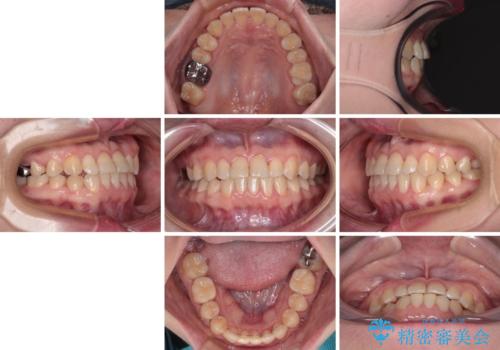

- 前歯の反対咬合を気にして来院された患者様です。

当院にて同様の咬み合わせを治療した方からのご紹介ということもあり、ご紹介者と同じワイヤー矯正で早めに治療を終えることを希望されました。

骨格的に下顎が前方に位置していましたが、歯列矯正で改善できると判断し、ワイヤー装置にて矯正治療を行うこととしました。

このような咬み合わせの方の多くは、舌の突出癖が強い傾向にあり、反対咬合改善後に開咬となってしまい、なかなか治療が終わらないことがあります。

こちらの患者様は、舌のトレーニングを治療開始前から徹底的に実践していただき、僅か8ヶ月という短期間で治療を終えることができました。